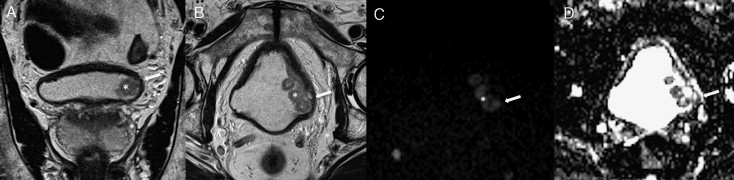

Exemplo de um tumor vesical localizado na parede lateral esquerda (*).

A‐ T2 coronal

B‐ T2 axial

C‐ DWI (b1200)

D‐ mapa ADC

Nas sequências T2 observamos tumor vegetante, de sinal intermédio implantado na parede lateral esquerda da bexiga, que infiltra profundamente a parede vesical, condicionando descontinuidade focal da linha de hipossinal característica da muscularis própria, traduzindo tumor músculo‐invasivo. Estes achados são corroborados pelo estudo funcional de difusão, documentando‐se tumor com hipersinal em DWI e hipossinal no mapa ADC (setas).